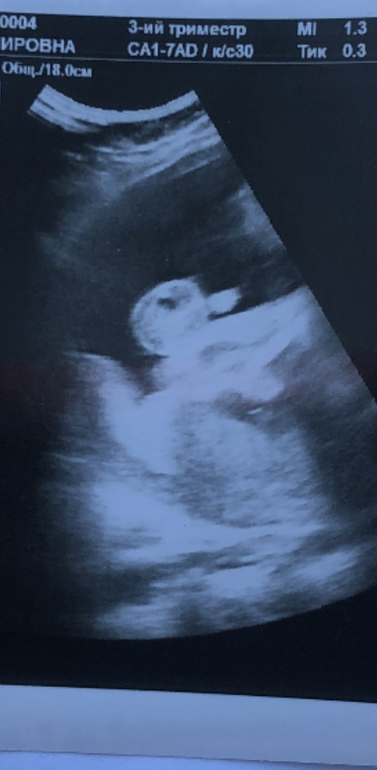

Всем привет ) в 20 недель была на узи и попросила написать пол ребёнка на листике и в конверт ) сделали дома семейное гендер пати и узнали что ждём вторую принцессу ) дочь была очень рада как и муж … а я почему то бужа уверена что там парень 😁 на днях ходила на 3 скрининг и доктор сам спросил: а кого я Вам говорил? Я сказала девочку ) и следом задала вопрос , а что , что-то выросло ? И мне сказали очевидно это мальчик 🤭 и дали вот такой снимок ) я вот теперь незнаю кого жду … думаю может опять там что-то к родам отвалится 🙈 а вы кого видите?